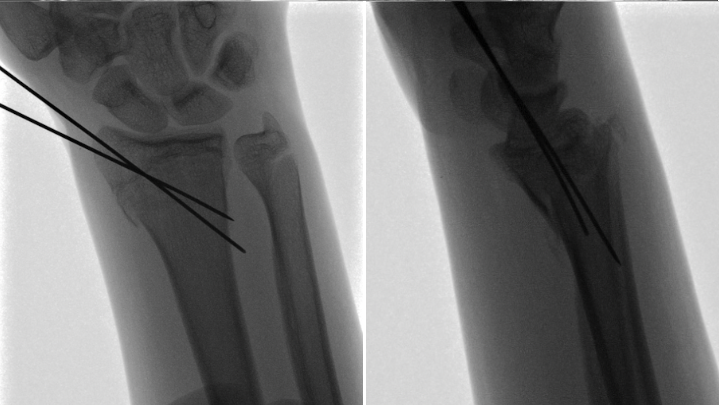

Patient one: A 14-year-old, right-hand dominant female presented to the emergency department (ED) with pain in her right wrist following a fall while roller-skating. No numbness or weakness was noted on the physical exam, and peripheral perfusion was normal. The patient had full extension and retropulsion of the right thumb. Imaging was obtained in the ED, demonstrating a non-displaced, Salter-Harris II distal radius fracture and avulsion of the right ulnar styloid process. No reduction was required. The patient was treated with a reverse sugar tong splint and discharged. The following day, she presented for an outpatient follow-up. Repeat imaging in the splint was obtained, demonstrating a Salter-Harris II distal radius buckle fracture [Figure 1]. The splint was removed and replaced with a short arm cast.